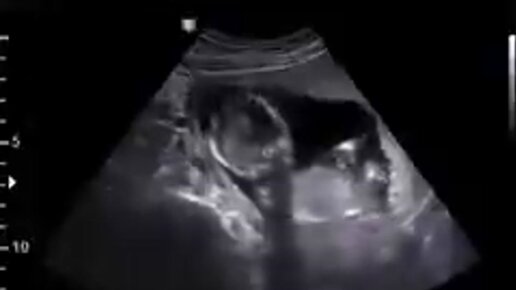

УЗИ Икота Плода В Утробе Матери (ВИДЕО)